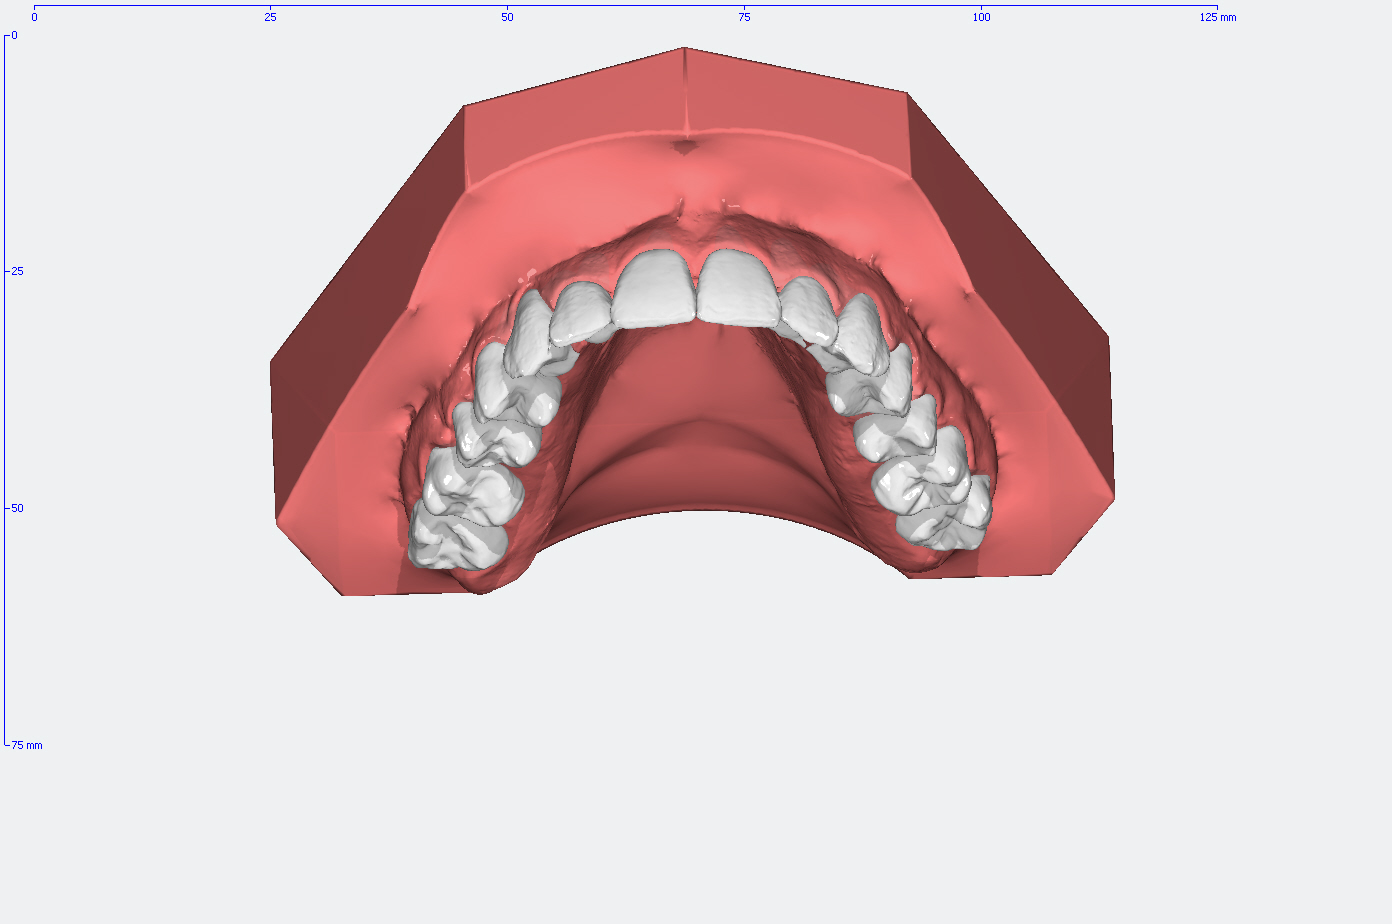

Die Entwicklung der Zahnstellung im Gebiß anhand von 3D Modellen

In den Abbildungen unten sehen Sie den Vergleich der Zahnstellung in den Gebissmodellen in der ursprünglichen Form und nach der kieferorthopädischen Behandlung.